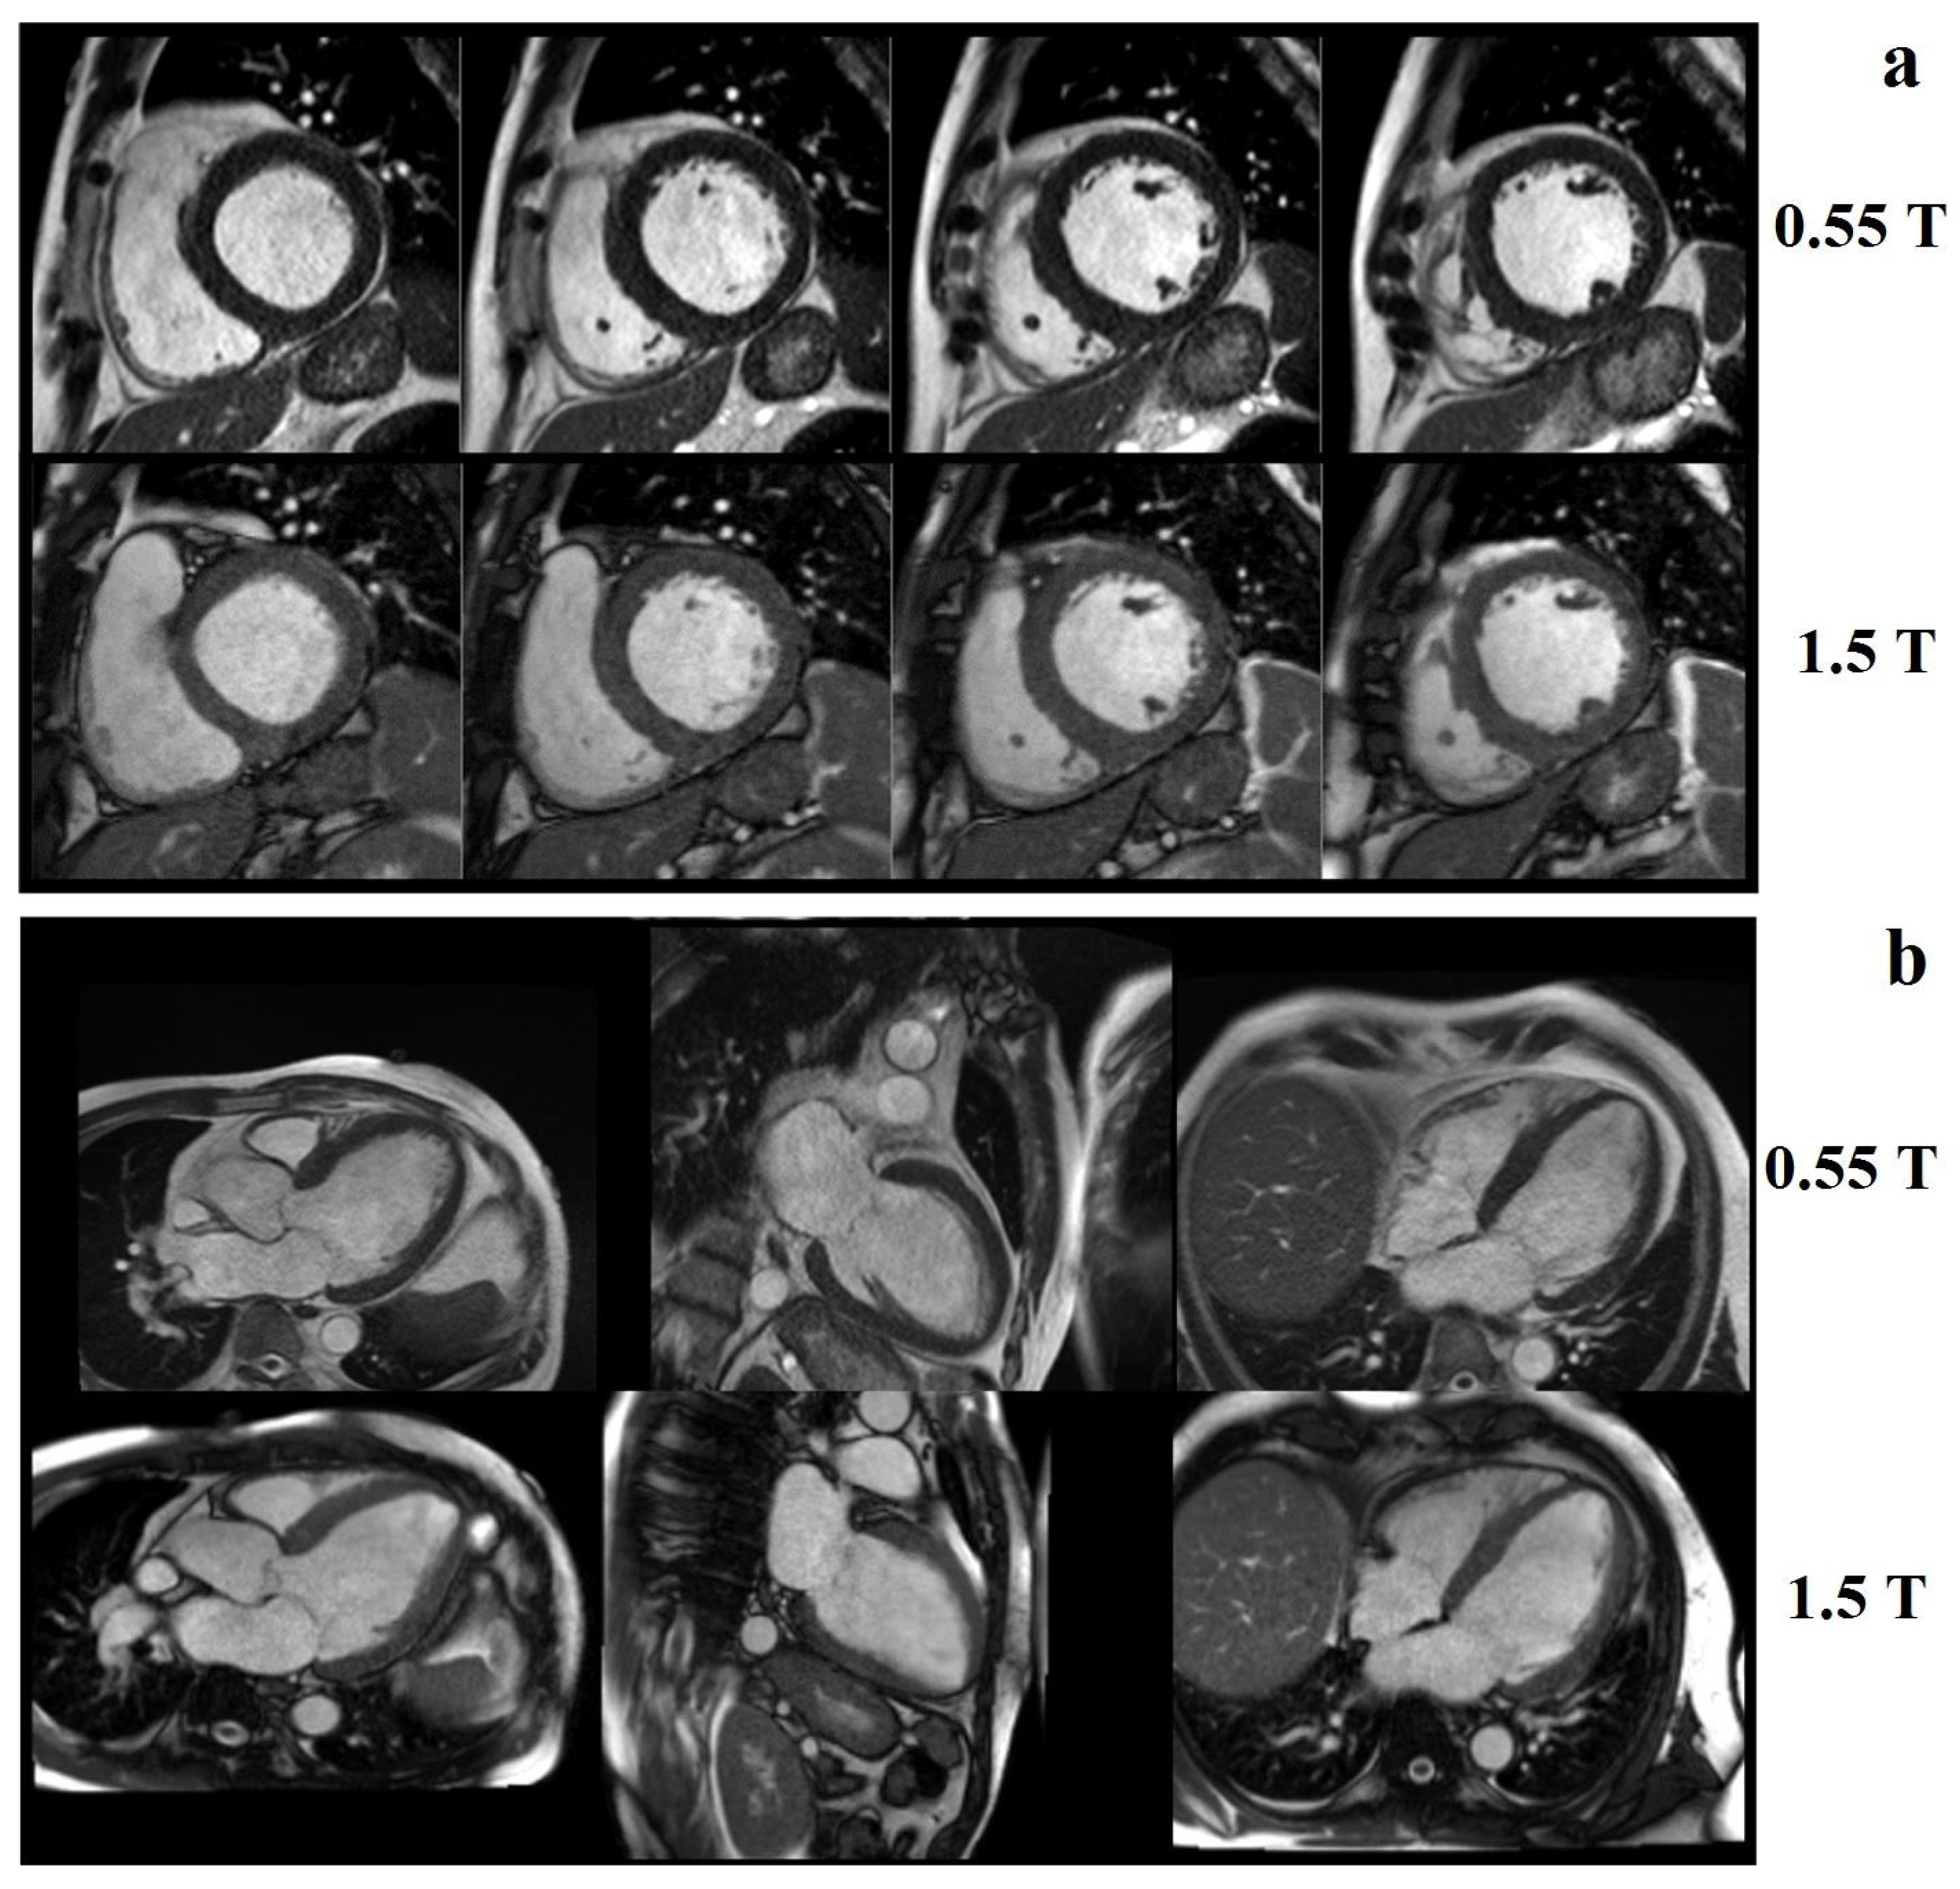

Low-field MRI has received increasing attention since low-field MR images have been shown to be diagnostically equivalent to 1.5 T images for specific applications [47]. Bandettini at al. [48] demonstrated that, by using a high-performance 0.55 T cardiovascular MRI system, it is possible to obtain good image quality, cardiac function, and quantification of volume compared to a standard 1.5 T scanner (Figure 10).

Figure 10. Examples of image quality at 0.55 T and 1.5 T breath-held, cine-steady, state-free precession: (a) short axis and (b) long axis slices from a patient with a nonischemic cardiomyopathy. Reprinted from [48].